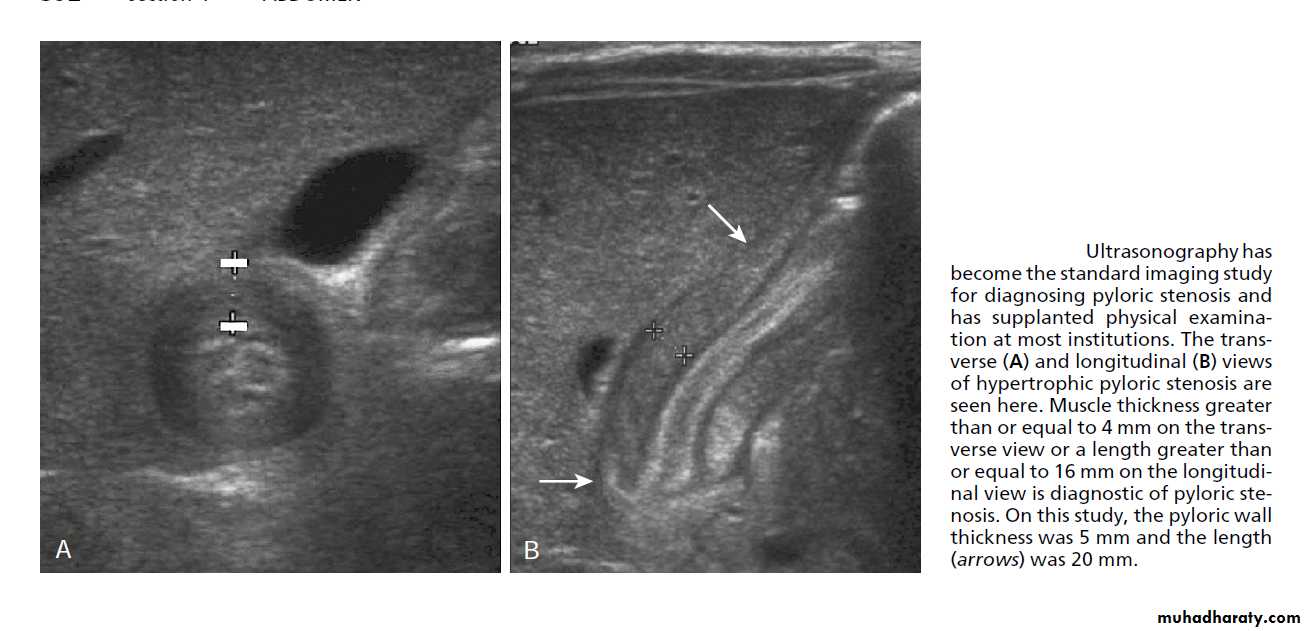

Clinical US Contrast Olive mass studyFeed test